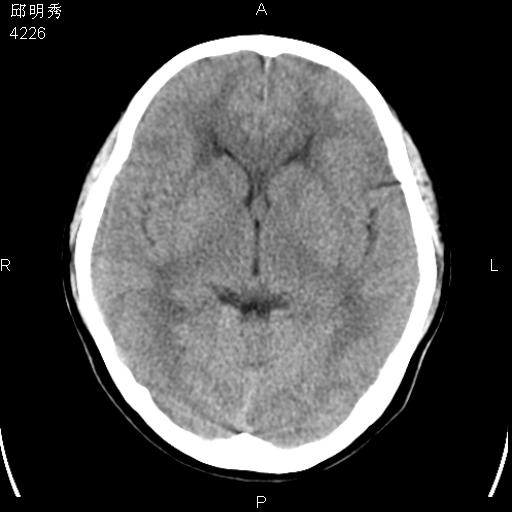

40f头晕十多天,右上肢麻木一天

脑白质变性或ms

脑白质脱髓鞘改变。

脑白质病;建议行mri检查。